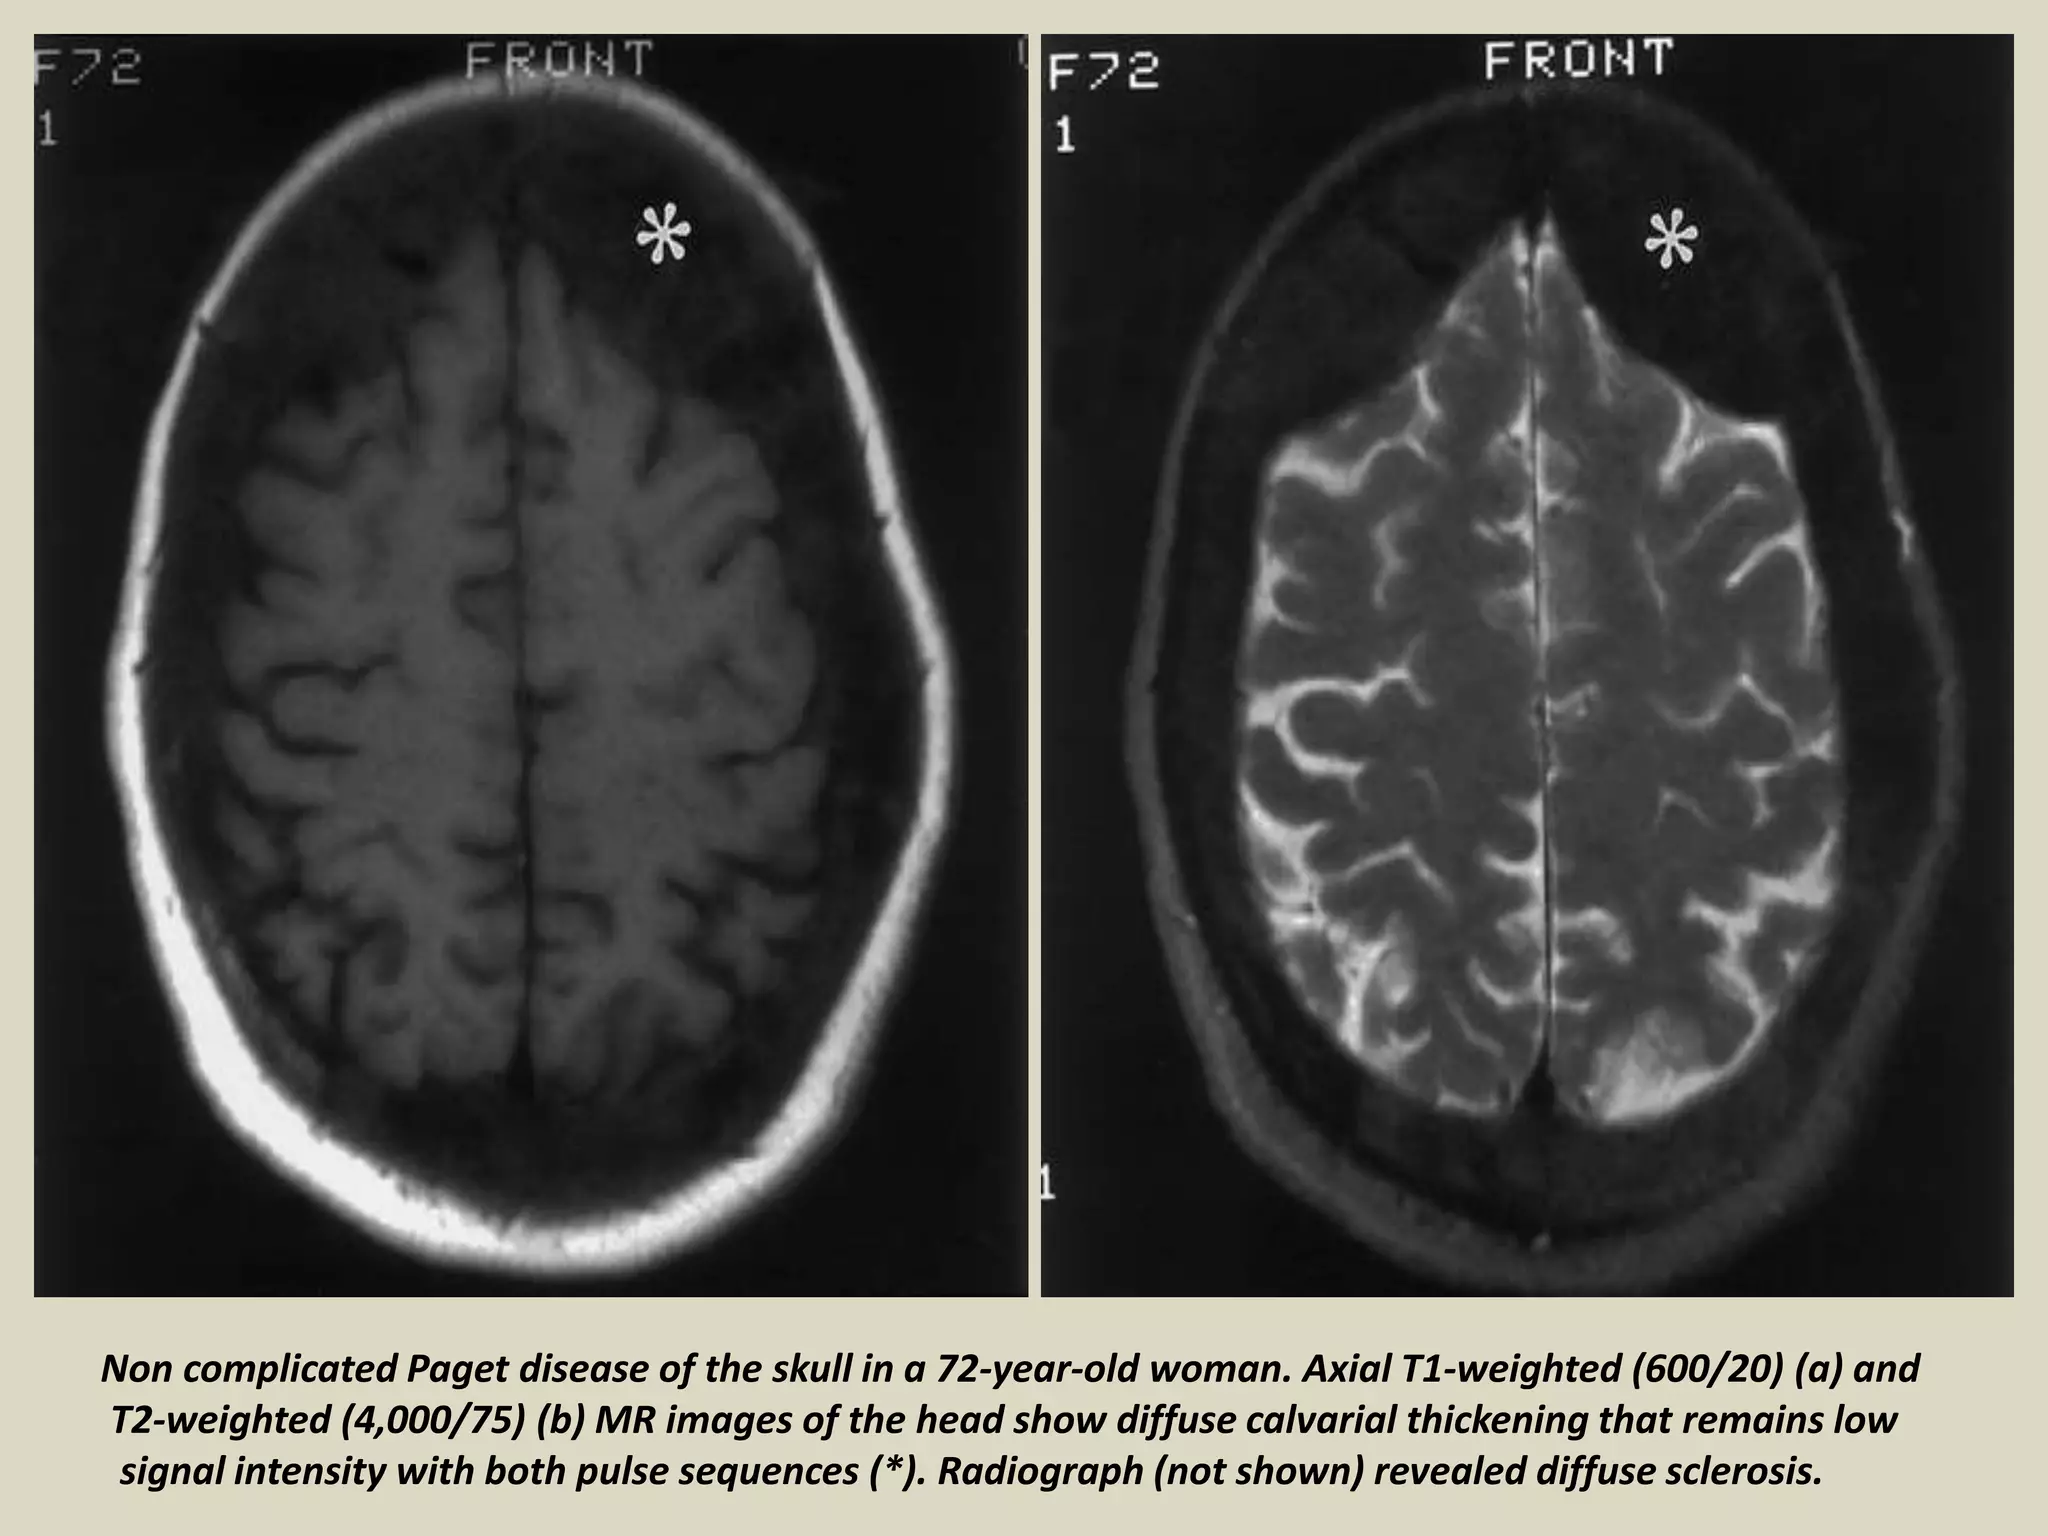

Non complicated Paget disease of the skull in a 72-year-old woman. Axial T1-weighted (600/20) (a) and

T2-weighted (4,000/75) (b) MR images of the head show diffuse calvarial thickening that remains low

signal intensity with both pulse sequences (*). Radiograph (not shown) revealed diffuse sclerosis.

Non complicated Pagetdisease of the skull in a 72-year-old woman. Axial T1-weighted (600/20) (a) and T2-weighted (4,000/75) (b) MR images of the head show diffuse calvarial thickening that remains low signal intensity with both pulse sequences (*). Radiograph (not shown) revealed diffuse sclerosis.